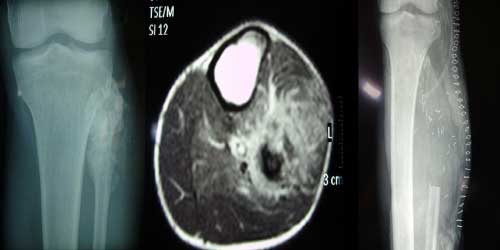

Omurga metastazı, kanserin ilk olarak iç organlarda gelişip daha sonra omurga kemiklerine yayılması sonucu oluşan bir durumdur. Çoğunlukla kan yoluyla sıçrayan bu tür metastaz, hastalarda sırt ve bel ağrısı gibi şikayetlerle kendini gösterir. Erken teşhis ve uygun tedavi yöntemleri, hastaların yaşam kalitesini artırmada kritik bir rol oynar.

Tedavide başarıyı artıran en önemli etkenlerden biri ameliyat öncesi iyi bir hazırlık ve cerrahi planlama yapmaktır. Her şeyden önce tanı doğru konmalı. Bunun için hasta iyi dinlenip, detaylı muayene edildikten sonra tetkikleri dikkatli incelenmelidir.